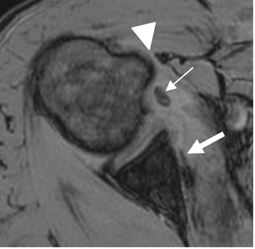

Fig 92. Pinzamiento interno anterior.

RM axial en FFE. Signos de pinzamiento anterior, con disminución del espacio coracohumeral. (Punta de Flecha). Hay luxación de la cabeza larga del biceps (Flecha delgada) y ruptura retraída del tendón del subescapular. (Flecha gruesa).